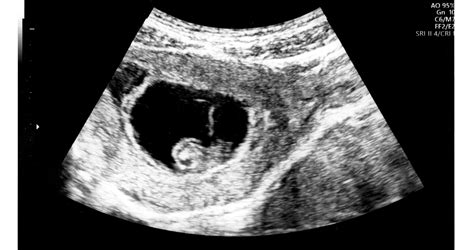

A diagnosztika az elmúlt évtizedekben jelentősen fejlődött. Míg korábban a méhnyak-terhességet gyakran csak műtét során ismerték fel, ma a korai terhességi ultrahangvizsgálat kulcsszerepet játszik a felismerésben. A transzvaginális ultrahang lehetővé teszi, hogy az orvos pontosan lássa a petezsák elhelyezkedését. Cervikális graviditás esetén a terhességi zsák a méhnyakcsatornában helyezkedik el, a méh ürege üres, a belső méhszáj zárt, és jellegzetes „homokóra” alak figyelhető meg.